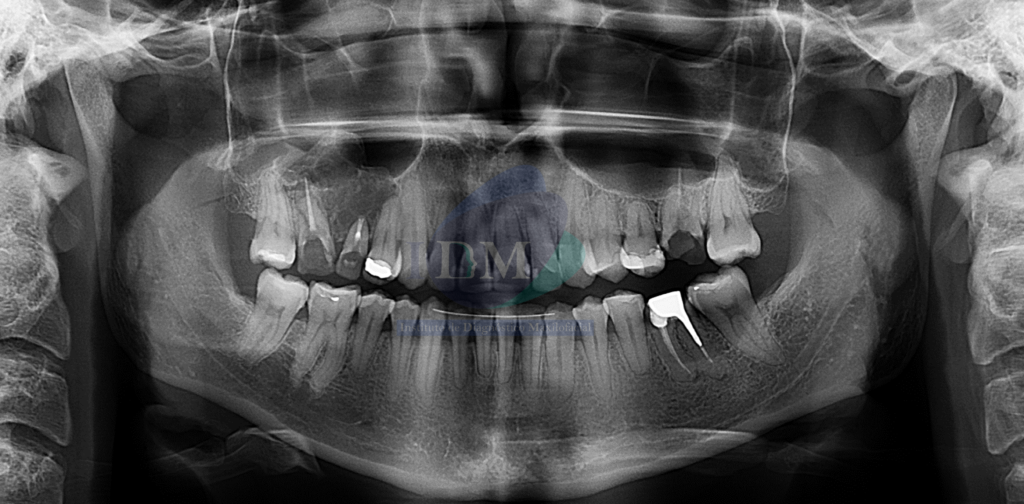

Radiografia Panorámica

A la evaluación de la radiografía panorámica una imagen radiolucida en zonas nasomaxilar derecha, de límites definidos y bordes parcialmente corticalizados. Comprometiendo ambas tablas óseas y piso de seno maxilar.